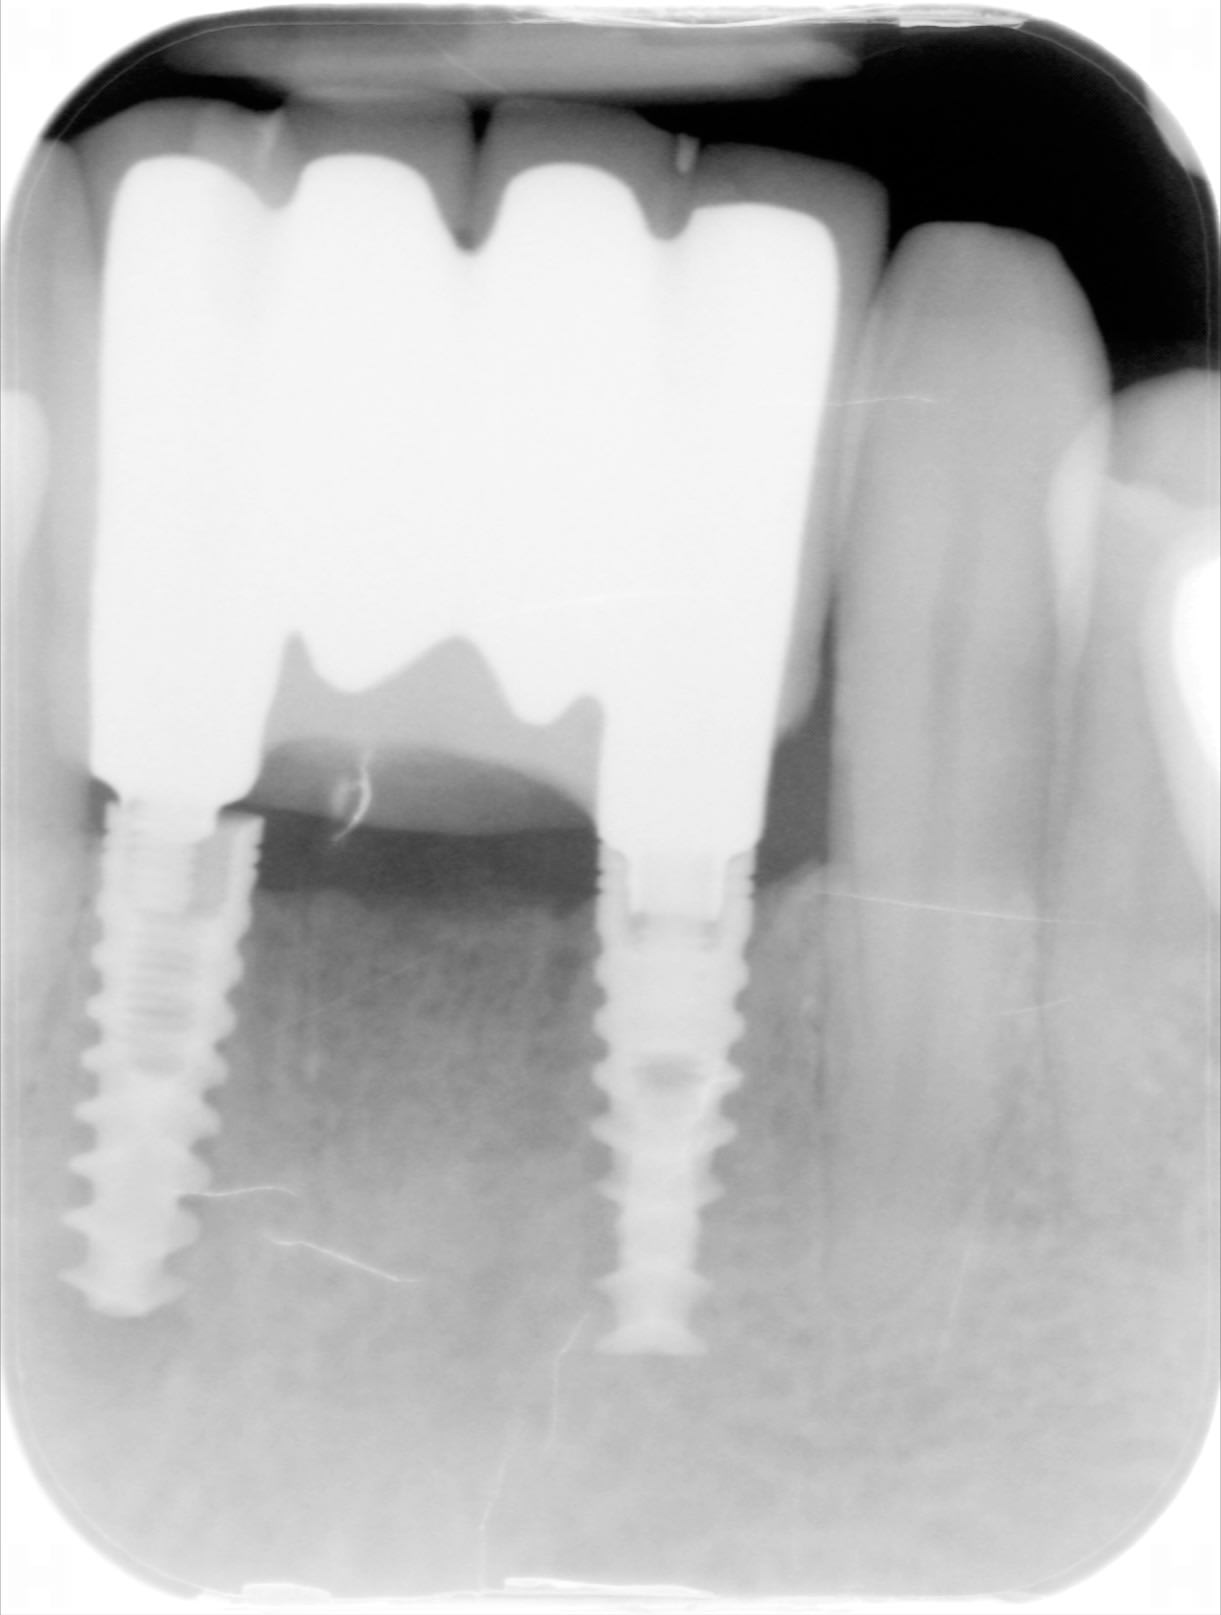

Patient arrivé de Paris cet été avec parodontale flambante!

ce bridge de 2 ans bouge ...., j' ai essayé de le renvoyer au poseur...

Pourriez vous m'aider pour la marque des implants?

normal que çà bouge...y a un côté pas vissé....;-))

quelque chose me dit que l'empreinte n'était pas bonne....;-))

sinon, c'est de l'alphabio

https://whatimplantisthat.com/implant/spi/

Oui j' avais bien vu le défaut de prothèse , c'est pour ça que j' ai essayé de lui expliquer que retourner voir le poseur avec la radio était la meilleure solution... J'espère qu'il ira...

Ca marche avec quels tournevis ces alphabio , STP